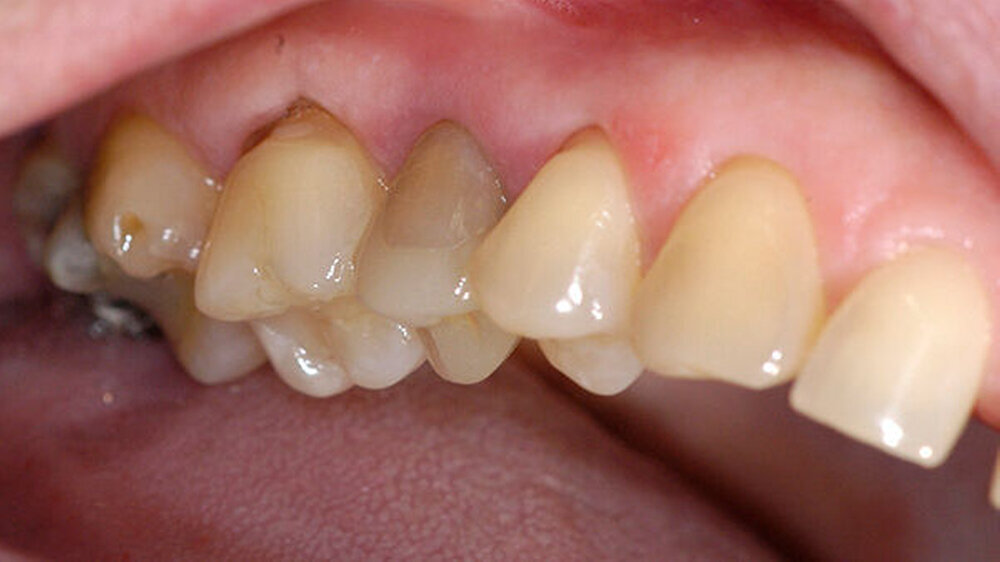

In der Poliklinik für Zahnerhaltung des Universitätsklinikums Münster war zwar die allgemeinmedizinische Anamnese unauffällig, doch zeigte sich klinisch nach Entfernung der vorhandenen mod-Glasionomerzementfüllung ein deutlicher Frakturspalt in mesial-distaler Ausrichtung am Boden der Kavität (Abbildung 1). Darüber hinaus war auf der Röntgenaufnahme des Vorbehandlers eine apikale Aufhellung zu erkennen (Abbildung 2).